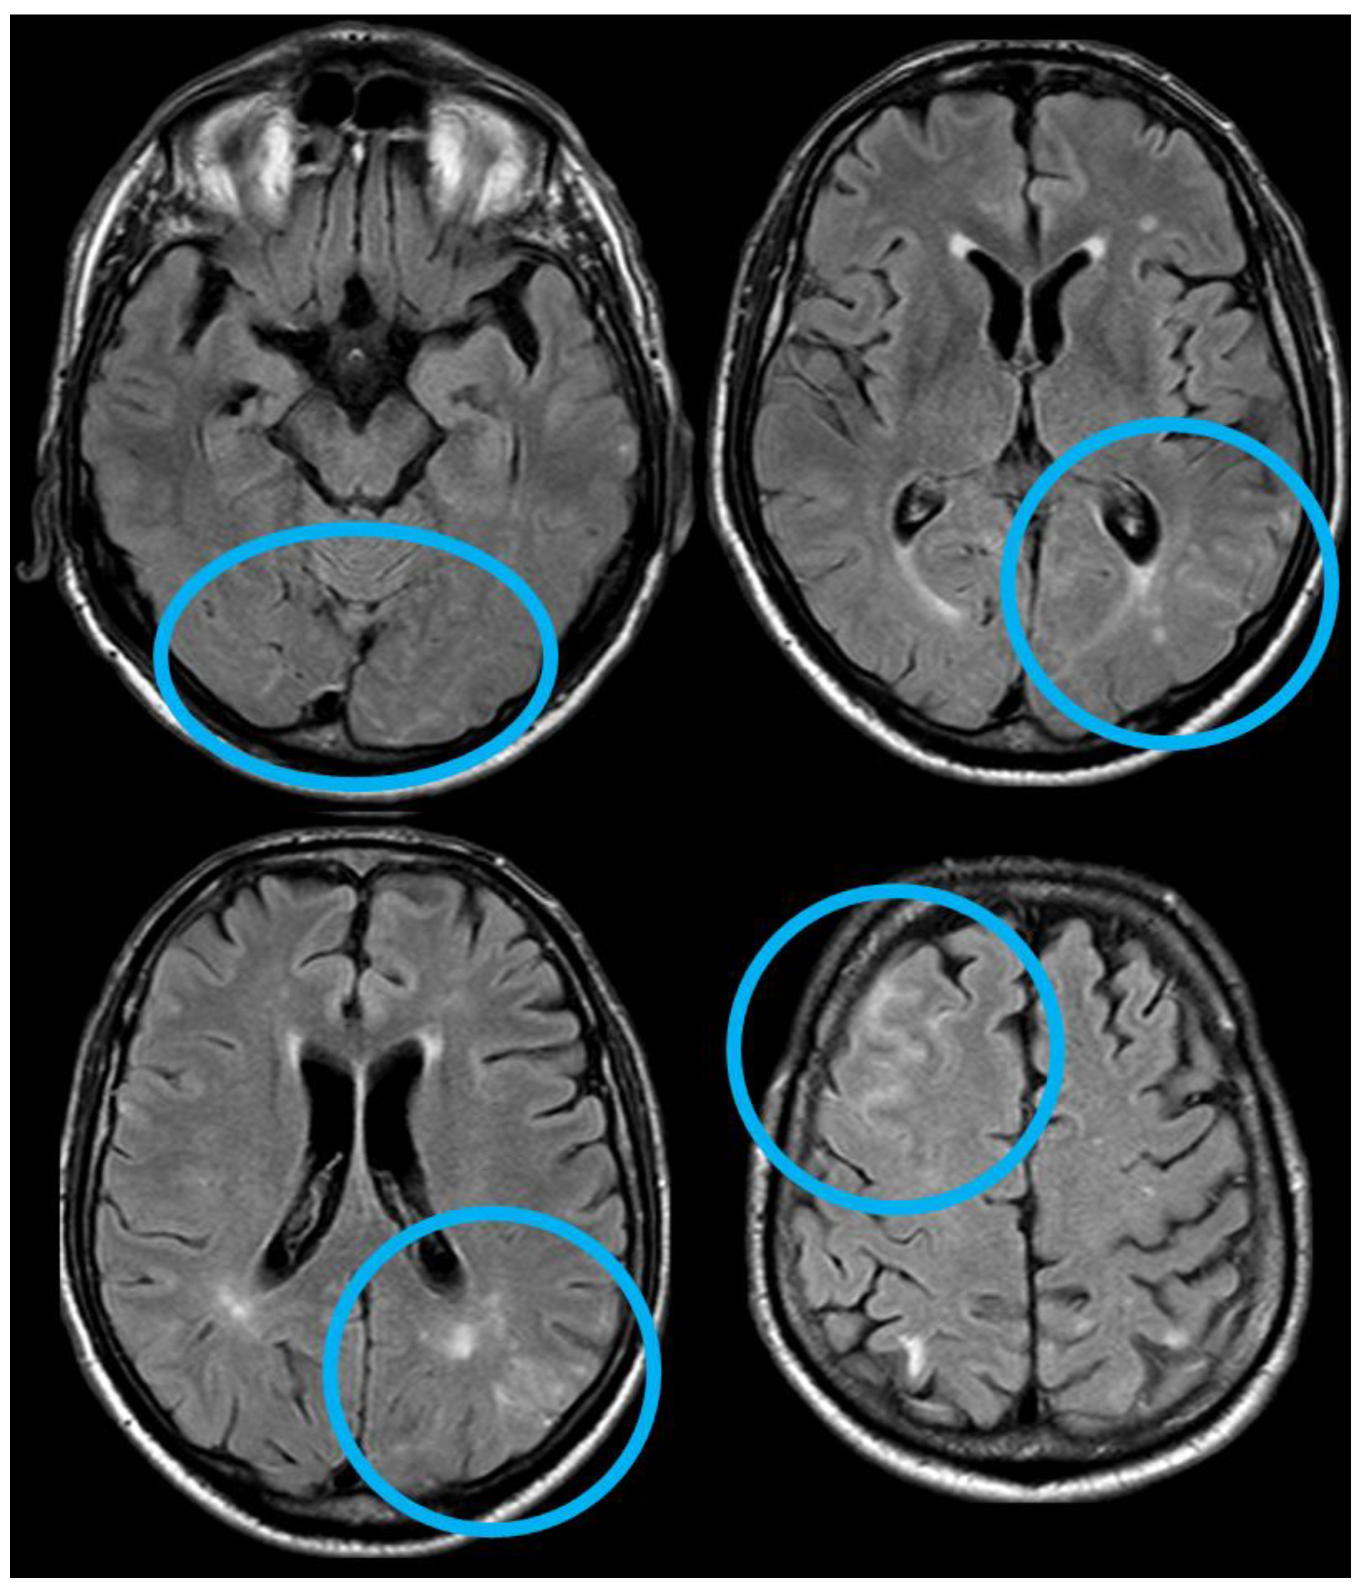

5. February 2017: First Recurrent CAA-Related Inflammation

6. December 2017: Recurrent SAH